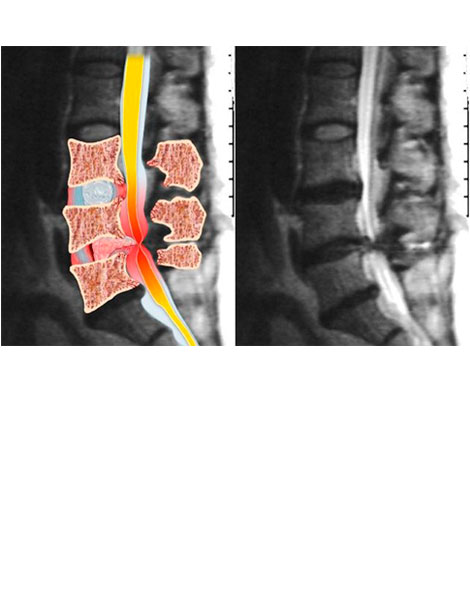

ESTENOSIS DEL CANAL LUMBAR

Estenosis se refiere a un estrechamiento de los agujeros o canales por donde viajan la medula espinal y las raíces nerviosas.

Los médicos muchas veces denominamos "compresión" a este estrujamiento.

Se visualiza (flechas rojas) como se ha reducido el tamaño del canal medular, lo que produce la compresión de las estructuras nerviosas que se encuentran en su interior